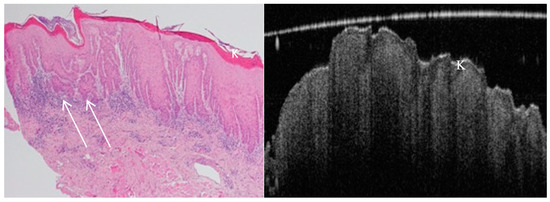

- Tsai, M.T.; Lee, H.C.; Lee, C.K.; Yu, C.H.; Chen, H.M.; Chiang, C.P.; Chang, C.C.; Wang, Y.M.; Yang, C.C. Effective indicators for diagnosis of oral cancer using optical coherence tomography. Opt. Express. 2008, 16, 15847–15862. [Google Scholar]

- Lee, C.K.; Chi, T.T.; Wu, C.T.; Tsai, M.T.; Chaing, C.P.; Yang, C.C. Diagnosis of oral precancer with optical coherence tomography. Biomed. Opt. Express. 2012, 3, 1632–1646. [Google Scholar] [CrossRef] [PubMed]